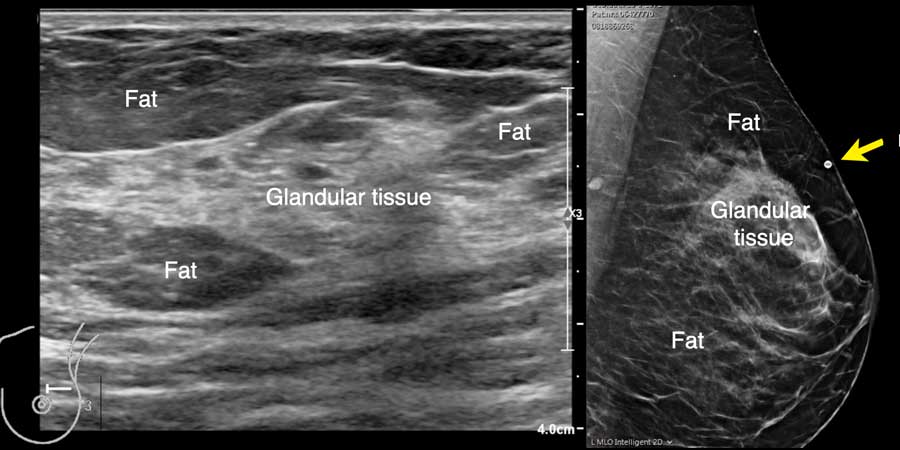

Đây là hình ảnh siêu âm bình thường của tuyến vú.

Lớp xám phía trên là da.

Tiếp theo là sự pha trộn giữa mô mỡ (tối hoặc giảm âm) và mô tuyến (xám sáng hoặc tăng âm).

Lớp có vân sọc phía sau mô vú là cơ ngực.

Phía sau hoặc sâu hơn so với xương sườn có một vùng đen hay bóng cản âm phía sau.

Phổi là lớp có thể quan sát sâu nhất.

Không khí trong phổi phản xạ hầu hết sóng âm, tạo ra một đường sáng hoặc tăng âm với bóng cản bẩn phía sau.

Siêu âm cho phép xác định thành phần mô vú: mô xơ tuyến đồng nhất – mô không đồng nhất – hoặc mô mỡ đồng nhất (hình).

Lưu ý rằng hình ảnh nhũ ảnh và siêu âm rất tương đồng nhau.

Trong cùng một tuyến vú có thể tồn tại các vùng có nhiều mô mỡ xen kẽ với các vùng chủ yếu là mô xơ tuyến, như có thể thấy trên video.

Khi quan sát đường bờ của mô tuyến (mũi tên), có thể hình dung rằng khi sờ nắn sẽ cảm thấy gồ ghề và đôi khi tạo cảm giác như có một khối u khi mô tuyến rất phát triển.